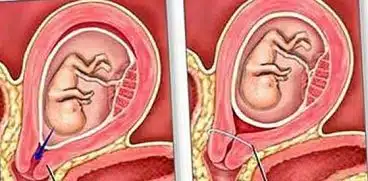

- Sarcina pe săptămâni

- Nașterea prematură